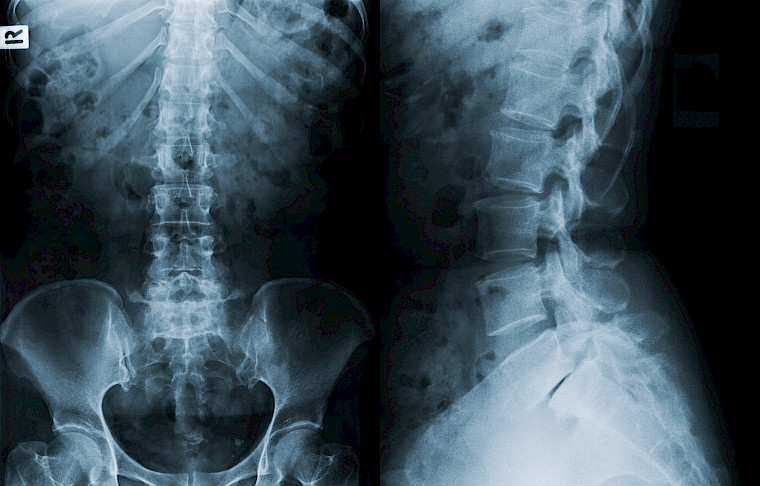

Digitales Röntgen

Sämtliche konventionelle Röntgenaufnahmen führen wir in digitaler Technik durch, inklusive Thorax-, Abdomen und Skelettaufnahmen. Die Röntgendokumentation erfolgt ebenfalls digital.

Das Angebot umfasst sämtliche konventionellen digitalen Röntgenaufnahmen für Thorax-, Abdomen- und Skelettaufnahmen, Ultraschalluntersuchungen für Weichteile, Ganzkörper-Computertomographie und MRI-Untersuchungen.